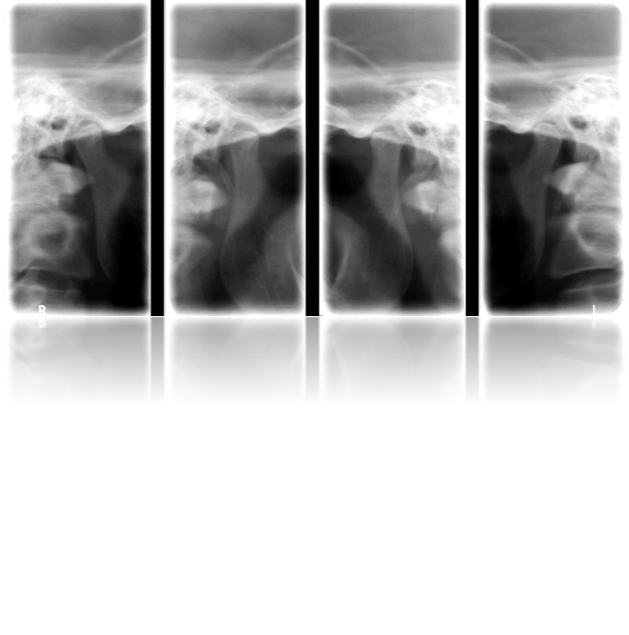

Descriere

Este utilizată pentru evidențierea patologiei articulare de natură inflamatorie, traumatică, tumorală, hiperplazică, atrofică etc. și poate fi efectuată cu gura închisă, deschisă sau în diverse grade de propulsie, în funcție de indicațiile medicului curant.

Acesta trimite pacientul la cabinetul de radiologie cu dispozitive speciale de mușcat care imobilizează mandibula în poziția dorită.